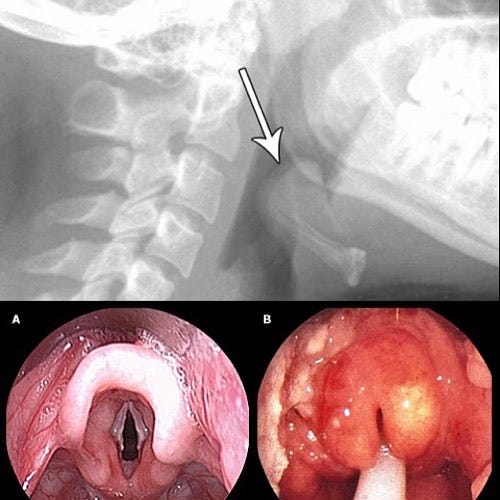

Tragically, Bill Bixby’s son, Christopher, developed epiglottitis, sudden trouble breathing, needed a tracheotomy to help him breath, but still died in the hospital.

Epiglottitis is typically caused by the Haemophilus influenzae type b (HiB) bacteria.